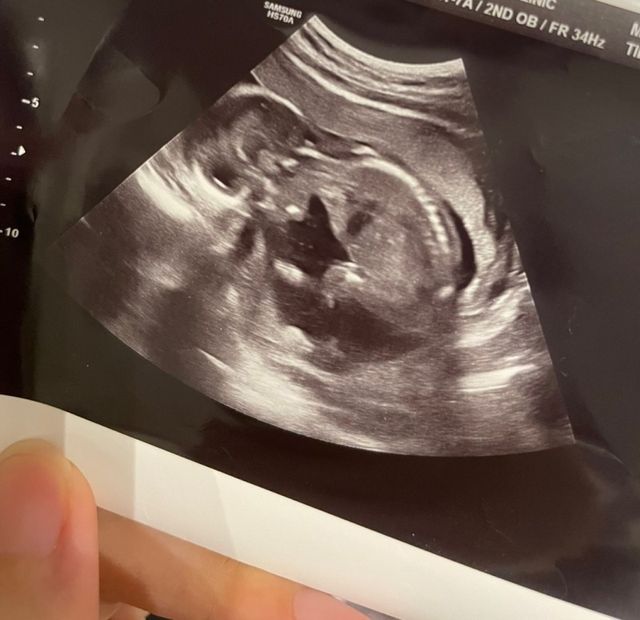

지난 7일 밤 유혜디는 자신의 블로그에 전 남자친구 미스틱에 대한 폭로 글을 올렸다. 유혜디는 지난 2021년 12월부터 올해 7월까지 미스틱과 교제했다며, 지난해 4월 미스틱이 동의 없이 피임을 하지 않아 임신을 하게 됐고 결국 22주 차에 낙태 수술을 했다고 털어놨다. 그 근거로 지난해 임신 당시 작성한 다이어리와 태아 초음파 사진, 유산 수술 동의서, 화장 증명서 등을 함께 공개했다.

BJ 유혜디가 폭로글과 함께 공개한 태아 초음파 사진 / 유혜디 블로그